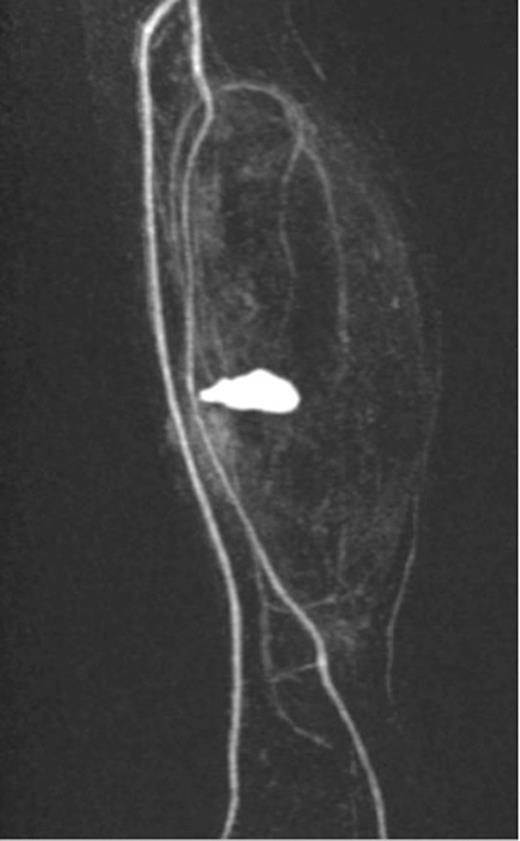

A 20-year-old man with no past medical history presented to the emergency department with non-displaced and closed transverse fracture of the left mid-tibial shaft and an intact fibula induced by a tackle during a football match. On examination, he had no neurovascular deficit and all crural pulses were palpable. His fracture was treated conservatively with a non-weight bearing above knee plaster cast later replaced by a below knee cast for a total period of 6 months. Upon examination during his attendance to the facture clinic, x-ray demonstrated no signs of fracture union. The subsequent magnetic resonance imagining (MRI) confirmed a nonunion of the fracture along with an ovoid 2.7 cm posterior compartment vascularized mass causing bowing of the interosseous septum with no evidence of avascularity of the bony margins (Fig. 1). This was confirmed to be a pseudoaneurysm originating from the PTA. An endovascular approach was adopted, and the pseudoaneurysm was injected with 2 ml of thrombin, filled with multiple coils and deployment of an angiography balloon (in the sac) (4 mm × 6 cm) for 7 min (Fig. 2). This resulted in complete cessation of the pseudoaneurysm with normal flow in the PTA (Fig. 3). The residual extravasated hematoma was later drained by an open approach. Follow-up x-ray (6 months) demonstrated complete union of the fracture site with no associated complications.

MRI images demonstrating the site, size and the origin of the PTA pseudoaneurysm.